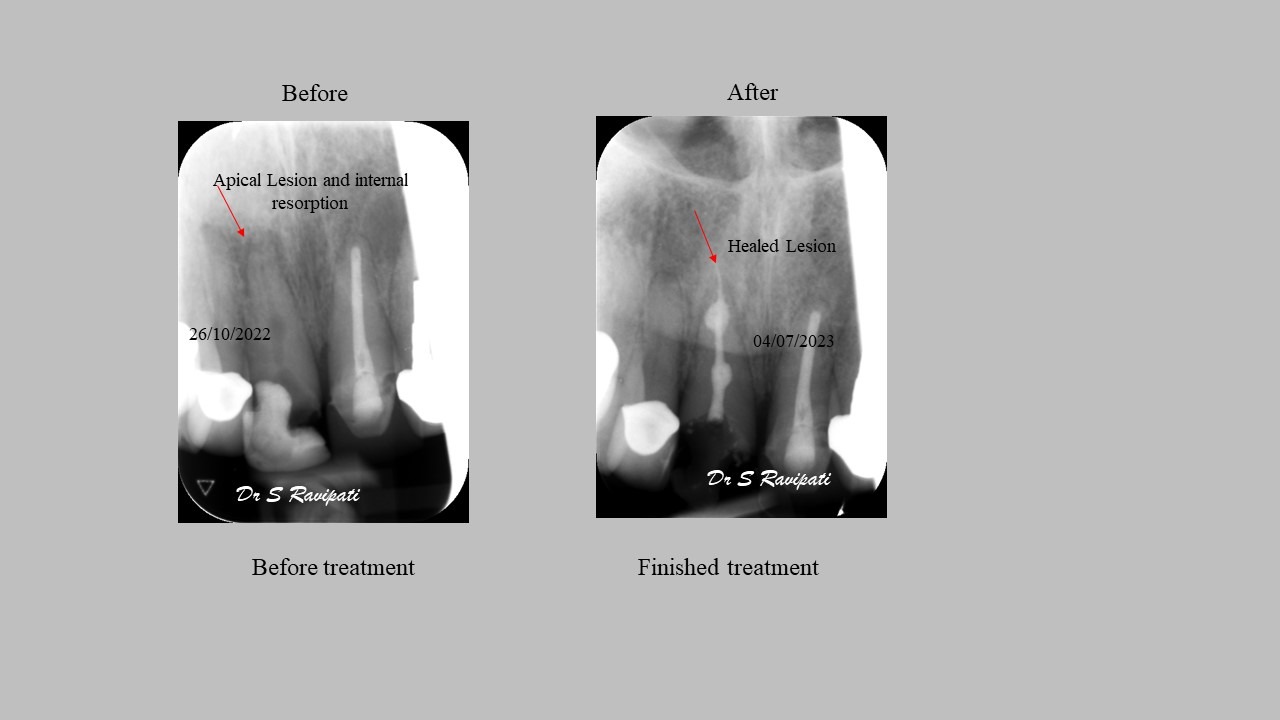

Studies have shown thorough cleaning with instruments, disinfection and sealing the canals contribute to the successful healing of the infection and this success is reported as 95%.